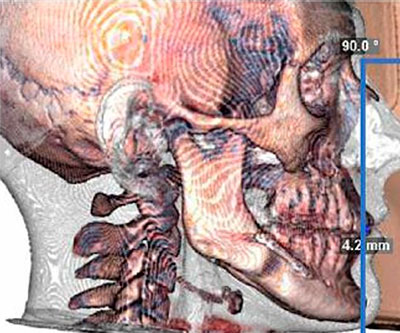

Efecto de la genioplastia estética en las vías respiratorias superiores

El artículo analiza el impacto de la genioplastia ósea estética aislada en el volumen de las vías respiratorias superiores (VAS).